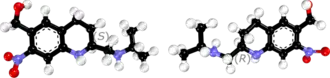

Oxamniquine contains a stereocenter and consists of two enantiomers. This is a racemate, i.e. a 1: 1 mixture of ( R ) - and the ( S ) - form:

| Enantiomers of oxamniquine | |

|---|---|

-Oxamniquin_Structural_Formula_V1.svg.png) (R)-isomer |

-Oxamniquin_Structural_Formula_V1.svg.png) (S)-isomer |